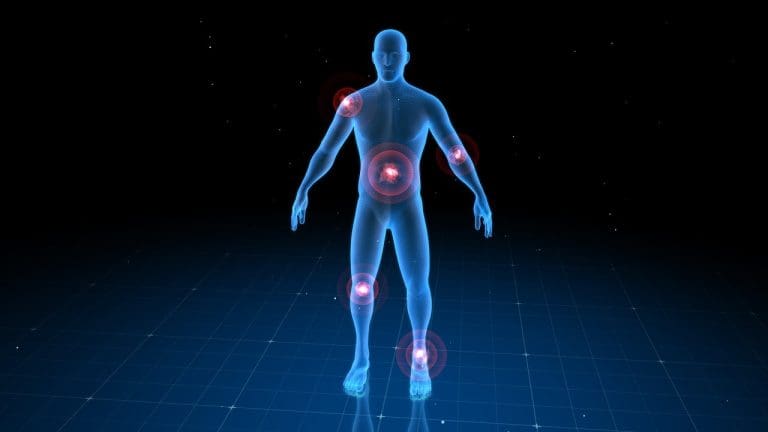

Feeling pain or pain in the lower extremities can really mess up your day. At Liv Hospital, we know how important it is to find out why you’re feeling this pain. Pain behind the leg can come from many things, like muscle strain, nerve issues, or blood flow problems.

Muscle strain and nerve problems are big reasons for leg pain. Blood flow issues can also cause it. Knowing what’s causing your pain helps us find the best way to make you feel better.

Pain in the back of the leg is common and can have many causes. It can range from muscle strains to complex neurological issues. To tackle this pain, we must first understand the anatomy and symptoms involved.

Joint and Bone-Related Causes

It’s important to know why pain behind the leg happens. Many conditions can cause this pain, making life harder for those who suffer from it.

Knee Joint Problems

Knee issues like sprains or tears can send pain to the back of the leg. These problems often come from sports injuries or age. Getting the right diagnosis and treatment is key to avoid more problems.

Hip Issues Referring Pain to the Leg

Hip problems, like osteoarthritis or fractures, can also cause leg pain. The hip is vital for moving around. When it hurts, it can make everyday tasks tough. We need to look at hip issues when we’re trying to figure out leg pain.

Osteoarthritis and Its Impact

Osteoarthritis is a disease that wears down joints, affecting the knee and hip. It causes pain, stiffness, and makes it hard to move. To manage it, we need to make lifestyle changes, do physical therapy, and sometimes surgery.